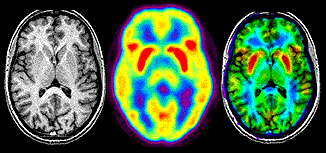

A finales de la década se introduce la tomografía de emisión y transmisión.

• Computarizada

Computarizada

Allan Macleod Cormack introdúcela Tomografía Computarizada.

• MRI

MRI

MRI fue creado por Paul C. Lauterbur.